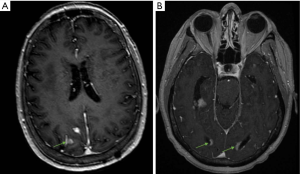

Patients may present with focal or diffuse disease on contrast-enhanced MR imaging of the brain and/or spine. There are variations in the radiographic appearance of LMD including linear/curvilinear enhancement, cranial nerve/nerve root enhancement, or nodular enhancement (27). Intracranial LMD tends to present along the cerebral convexities, cerebellar folia, basal cisterns and ventricular ependyma (Figure 1). Within the spine, all levels of the spinal cord are at risk, however LMD is commonly observed as enhancement and/or nodularity in the cauda equina (Figure 2).

In modern reports, the term nodular LMD has increasingly been used to acknowledge a distinct radiographic pattern of intracranial LMD that likely includes cases which may have previously been described as ‘bulky’ (7,42,43). Recently, a formal classification scheme was proposed by Turner et al. that identified two different radiographic patterns of LMD: classical LMD (cLMD) and a less consistently recognized nodular LMD (nLMD) (42). Patients with cLMD are described as having a pattern of enhancement that resembles “sugar coating” of the brain surface. Specifically, this may involve curvilinear or gyriform enhancement along the cerebellar folia, cerebral sulci, or cisterns and/or enhancement along cranial nerves without nodularity. In contrast, nLMD is characterized by focal enhancing nodules adherent to surfaces in contact with CSF including dural/pial surfaces, ventricles, tentorium or hypervascular dural tails. This classification is specific to intracranial LMD and does not address nodular spinal lesions.